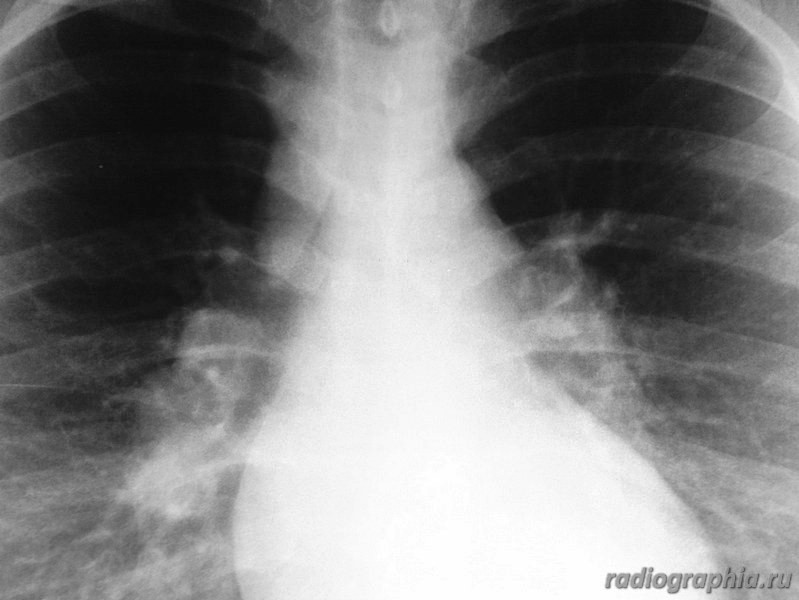

Рентгенография ОГК. Женщина средних лет.

интересует предыдущая рентгенодокументация (если есть :lol: ), анамнез заболевания. На момент осмотра больше данных за расширение легочных артерий , возможно начальные рентгенпризнаки развивающегося идиопатического легочного фиброза.Саркоидоз со стопроцентной уверенностью тоже исключать не стала бы.

Расширение верхнего средостения, широкие корни. У пациентки диагностирована лимфома. Была выполнена медиастиноскопия с забором лимфатических узлов на морфологию.